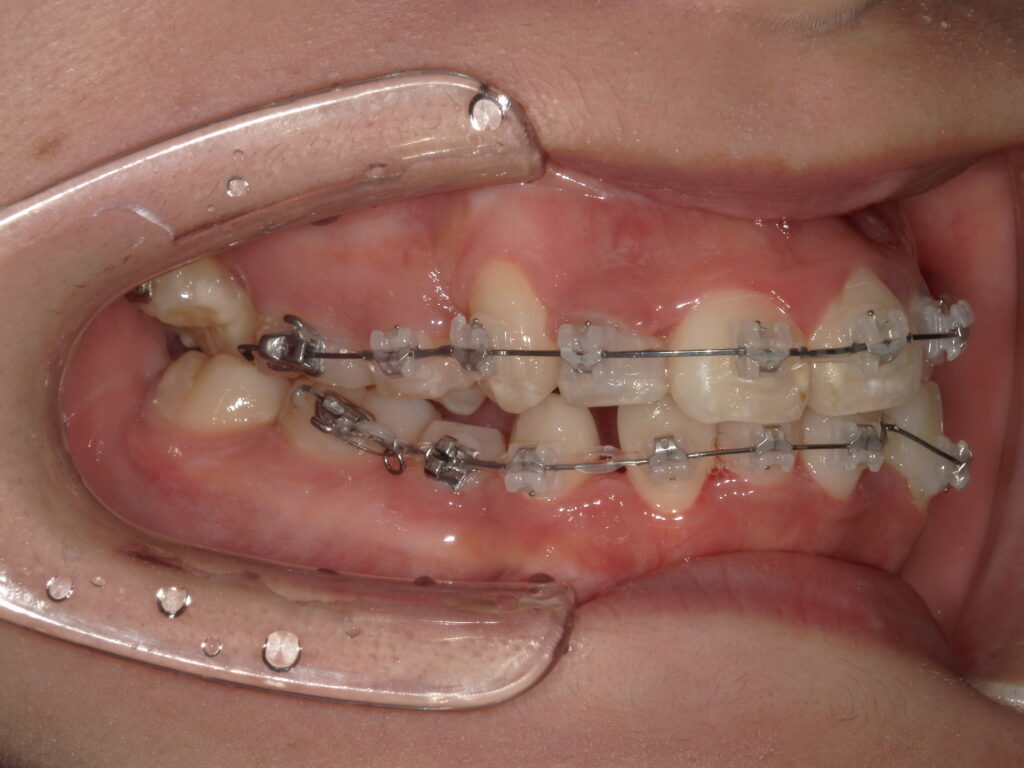

【治療経過】八重歯矯正を始めて4か月後の歯並び変化

【治療経過】八重歯矯正を始めて7か月後の歯並び変化